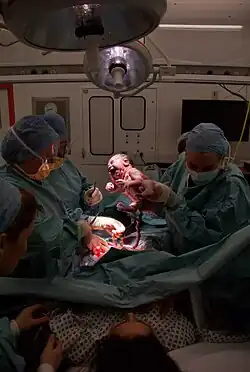

Nach der Geburt kann das gesunde Neugeborene vom Geburtshelfer oder der Mutter selbst auf ihre Brust oder ihren Bauch gelegt und warm zugedeckt werden, um das Bonding und erstes Stillen zu ermöglichen bzw. die Geburt der Plazenta zu erleichtern. Will die Mutter nicht stillen, kann das Kind in dieser Zeit auch zunächst dem Vater übergeben werden, um dessen Bindung an Mutter und Kind zu bestätigen oder zu festigen.